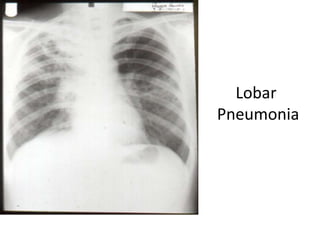

TB – A Multi-system Infection

Primary

Lobar

Pneumonia